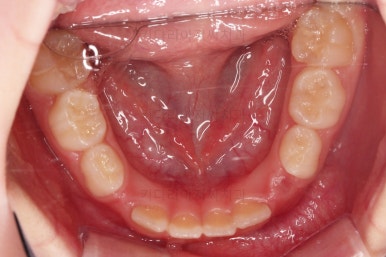

장치 사용 4달째 모습입니다.

벌써 개방교합이 개선되고 있고, 반대교합도 많이 좋아져서 거의 위아래 앞니가 비슷한 위치까지 왔네요.

왼쪽 하단 사진의 어금니에 있는 금속성 장치는 band & loop(밴드 앤 루프)라고 하는 공간유지장치인데요. 오래 써야하는 유치가 일찍 빠지는 바람에 그 공간을 잡아두는 장치입니다.